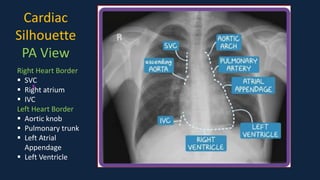

PPT - NORMAL HEART CONFIGURATION PowerPoint Presentation, free download ...

PPT - Introduction to Thoracic Radiology PowerPoint Presentation, free ...

Cardiac Silhouette - The American Journal of the Medical Sciences

Recognizing Adult Heart Disease | Radiology Key

The upper part of cardiac silhouette as seen in the chest radiograph ...